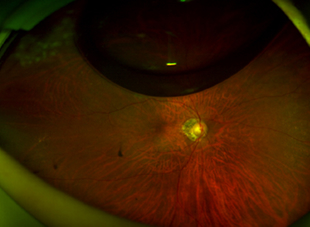

수술 전 사진

Before Surgery

수술 후 2일 사진

2 Days Post-Op

(Air 80%)

수술 후 7일 사진

7 Days Post-Op

(Air 30%)

수술 후 10일 사진

10 Days Post-Op

(Air 0%)